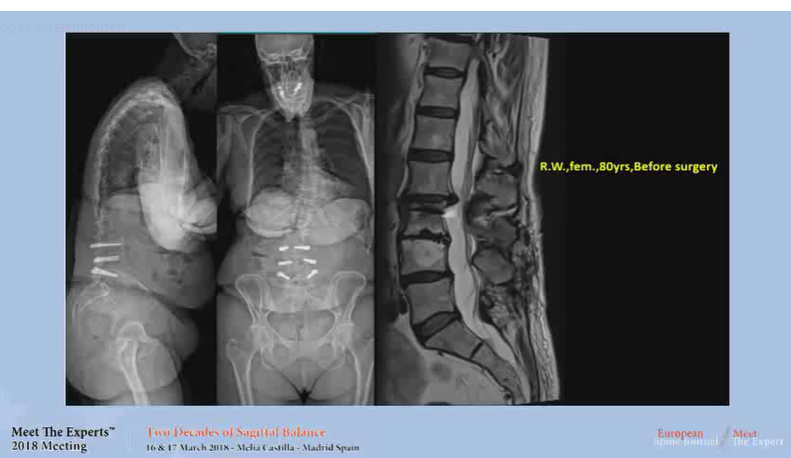

• Sagittal balance; case presentation

Sagittal balance; case presentation

Two decades of Sagittal Balance

Meet the Experts 2018